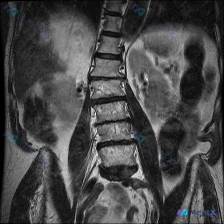

整理到一张腰椎MRI T2加权像冠状位的资料,大家第一眼可以先看看:

- 脊柱序列向左侧凸,顶椎大概在L2-L3水平,看起来有结构性改变

- 多个椎间隙(尤其下腰段)变窄,且凹侧更紧缩,椎间盘信号普遍减低

- 部分小关节区有骨赘、信号异常

- 椎体终板附近有斑片状信号不均